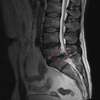

Le terme lombalgie désigne une douleur localisée dans le bas du dos, au niveau des vertèbres lombaires. Deux types de lombalgies sont à distinguer :

• Les douleurs lombaires aiguës, très connues dans la population sous le terme « lumbago ». Les douleurs peuvent être localisées, ou bien irradiantes, dans les jambes, appelées « sciatiques ».

• Les lombalgies chroniques lorsque la douleur persiste plus de 3 mois.

La plupart du temps, les lombalgies sont sans gravité, ce qui ne remet pas en cause l’importance de la douleur. Mais parfois, les douleurs sont d’origine pathologiques (la hernie discale / la scoliose / l’arthrose / l’ostéoporose ) d’où la nécessité de consulter un professionnel qui saura vous orienter.

Hernie Discal : des résultats très positifs

Une étude scientifique d’intérêt «  Incidence of Spontaneous Resorption of Lumbar Disc Herniation: A Meta-Analysis » (1)  vient d’être publiée sur l’incidence des résorptions non chirurgicales des hernies discales lombaires. Elle fait actuellement beaucoup de bruit dans le domaine médical.

Il s’agit d’une revue systématique de la littérature scientifique avec méta-analyse des différentes études cliniques publiées sur le sujet. Ce type d’étude est considéré comme constituant le plus haut niveau de preuve en matière scientifique. La méta-analyse, se propose de tirer une conclusion globale en combinant les résultats de plusieurs études indépendantes.

Conclusion après analyse : Il apparaît qu’en moyenne 66.66 % des hernies discales lombaires se résorbent sans chirurgie . Une étude anglaise s’étalant sur 56 mois (la plus longue de ces 5 études) , a retrouvé une taux de résorption de 83 % !

Dans leur discussion, les auteurs insistent sur ce taux de résorption important pour rendre prioritaire le traitement conservateur (non chirurgical) . L’économie réalisée sur les coûts est dans l’intéret des patients , des organismes d’assurance et de la société en général. Les chiropracteurs tiennent historiquement une place centrale dans la prise en charge conservratrice de ces patients

Cette étude est extrèment positive, et doit pouvoir rassurer d’avantage nos patients. Nous avions déjà publié un petit article ( Pourquoi ne pas focaliser sur votre hernie discale?) afin de relativiser les craintes face à cette pathologie, voilà encore d’avantage d’eau apportée au moulin de la démystification de la hernie discale …